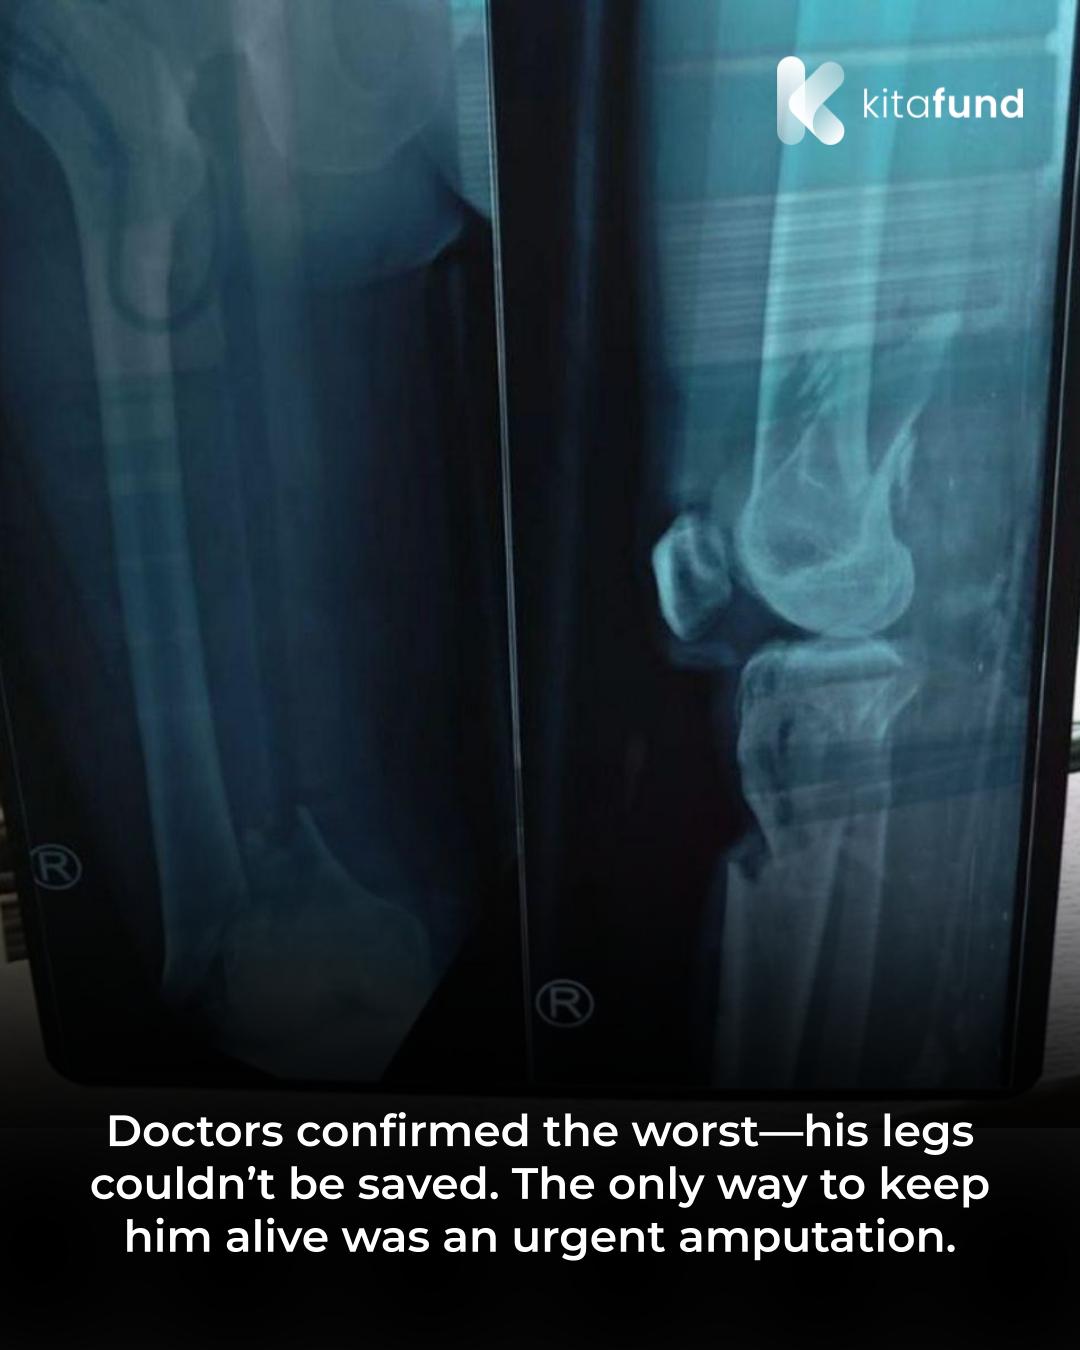

The devastating news reached his heavily pregnant wife—Pak Anjar lay unconscious in the ER, covered in blood after being hit by a reckless driver. Both of his legs were severely damaged—bones, nerves, and blood vessels completely shattered beyond repair. His only chance of survival is an amputation to prevent further complications from spreading to his vital organs. But how can they afford it? His daily wage as a laborer barely covers their basic needs, and now he’s supposed to welcome his first child…

Doctors confirmed the worst—his legs couldn’t be saved. The only way to keep him alive was an urgent amputation. With no other option, Pak Anjar and his wife had to accept this heartbreaking reality. But the hospital bills were beyond their means.